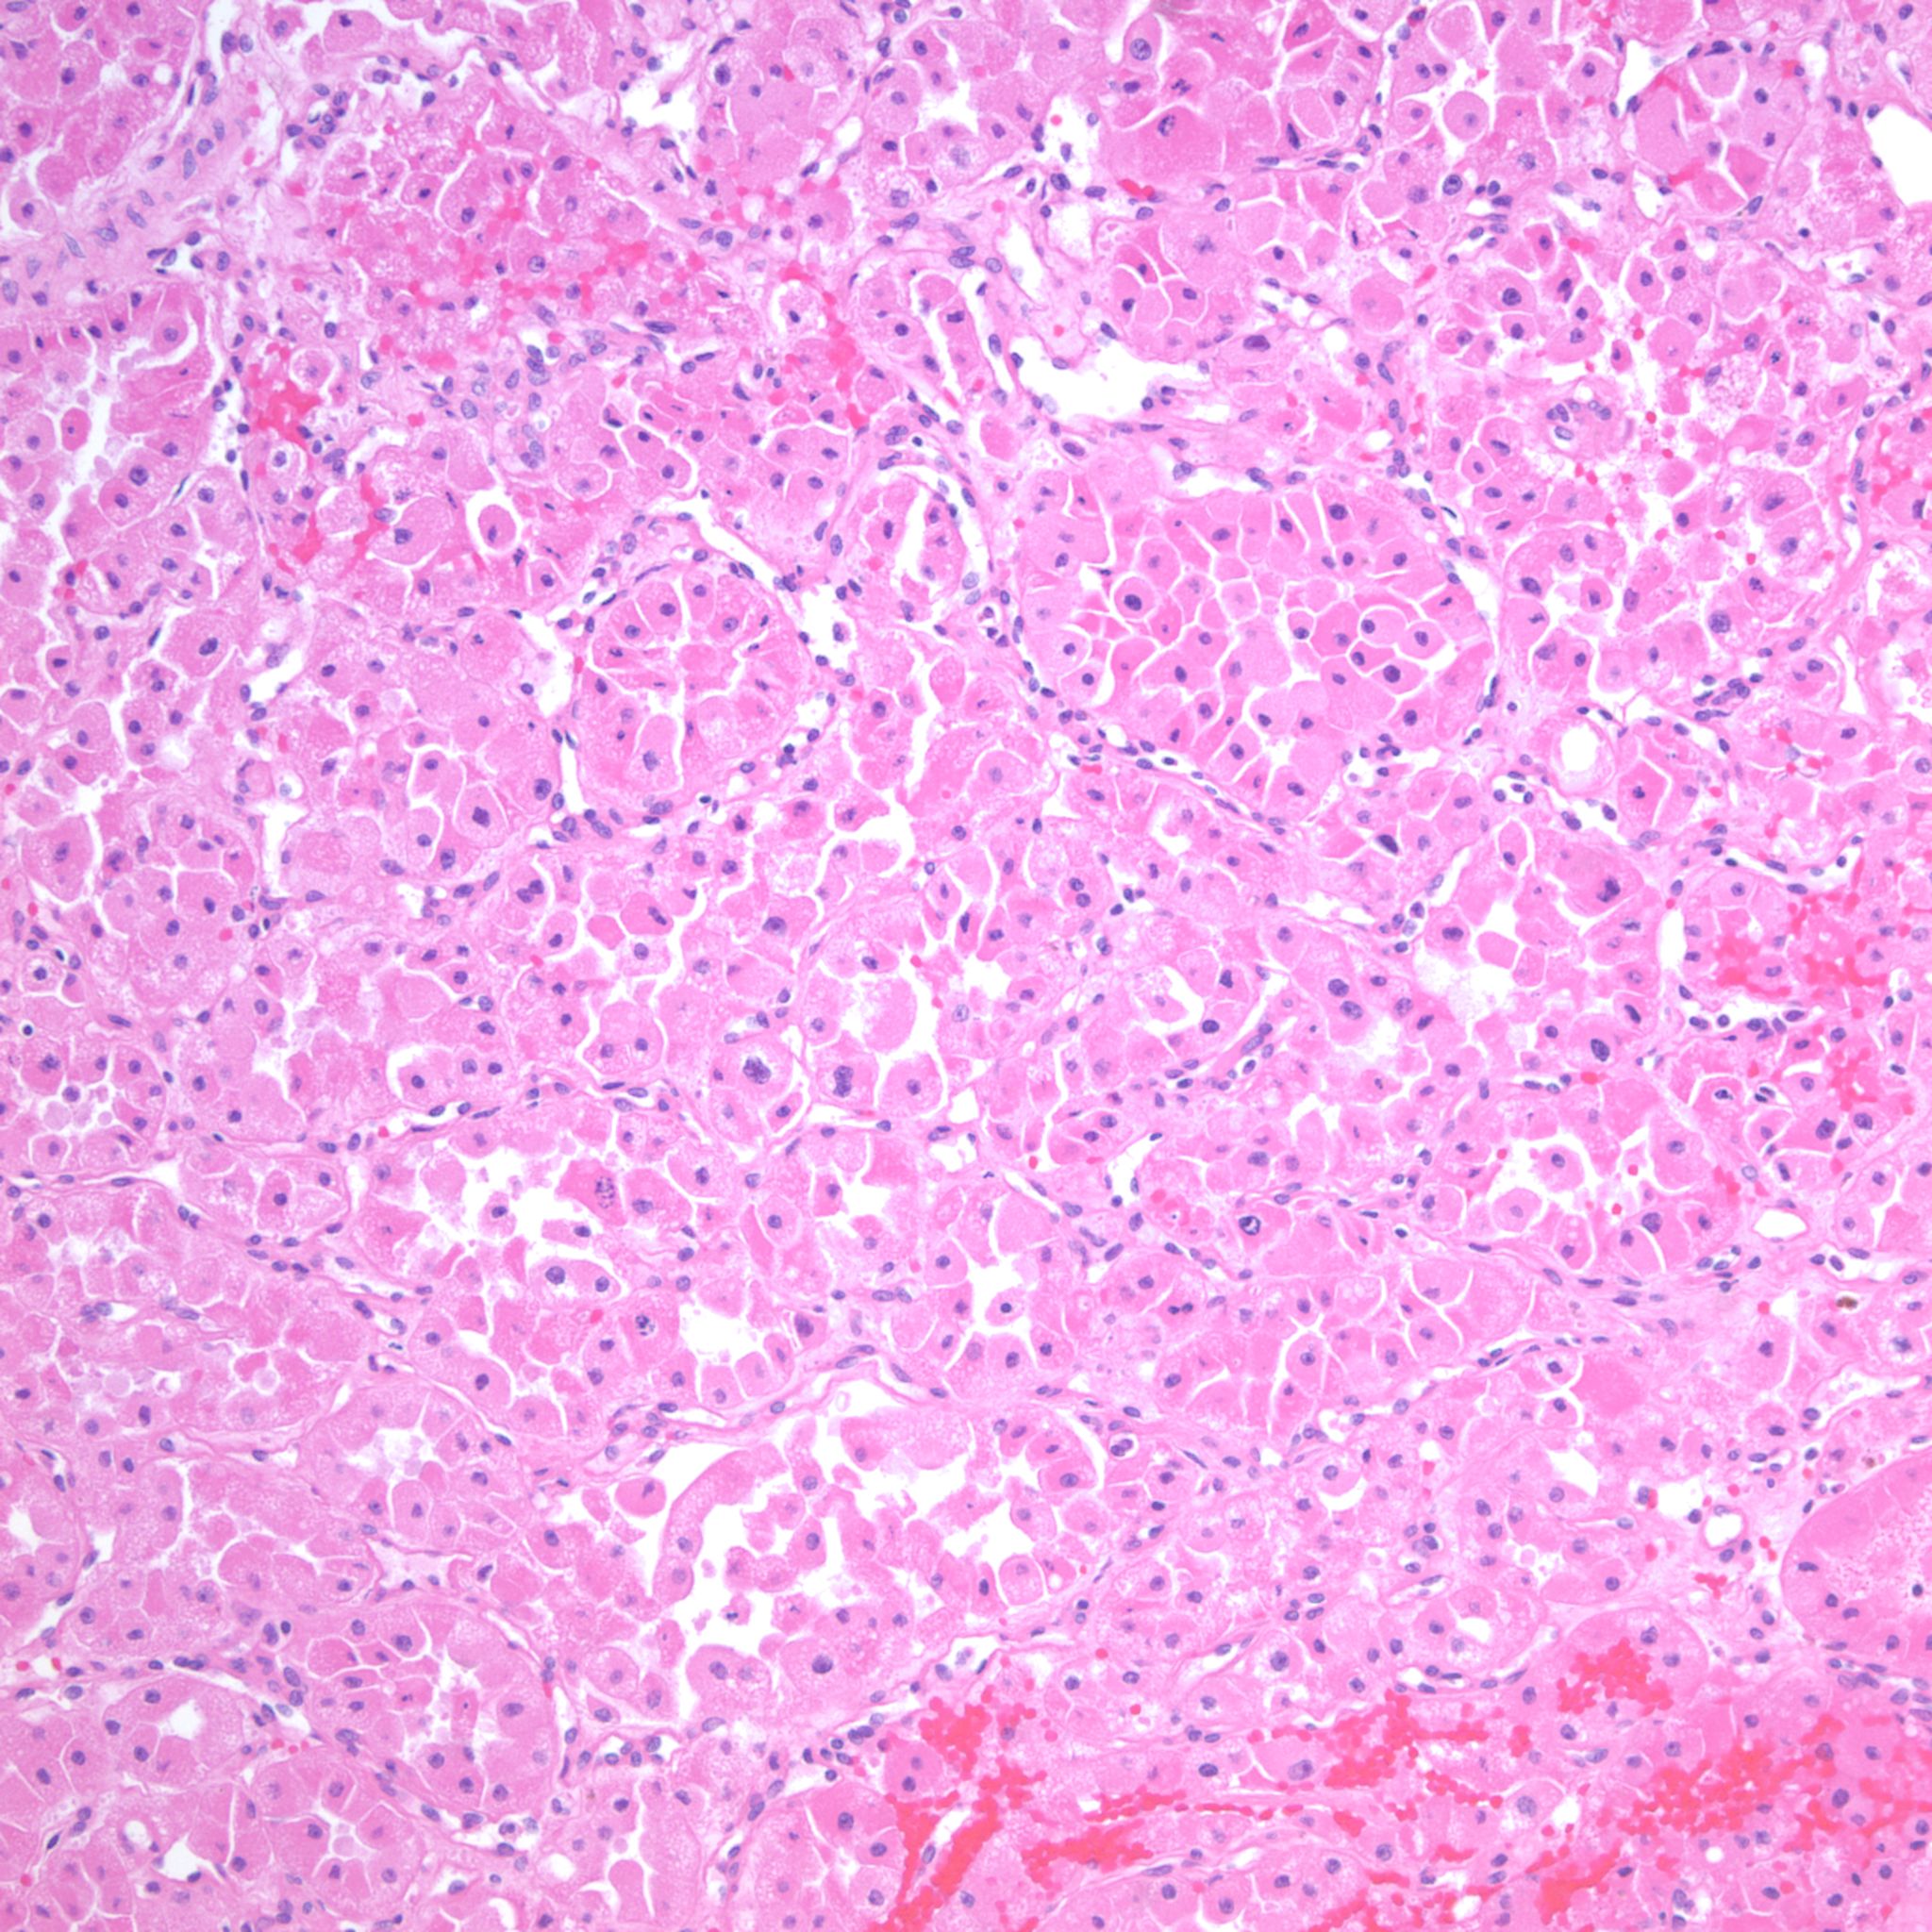

Renal tumor grading

Case ID: 1210